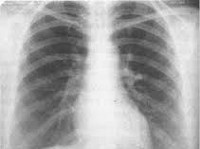

J84.1 Другие интерстициальные легочные болезни с упоминанием о фиброзе